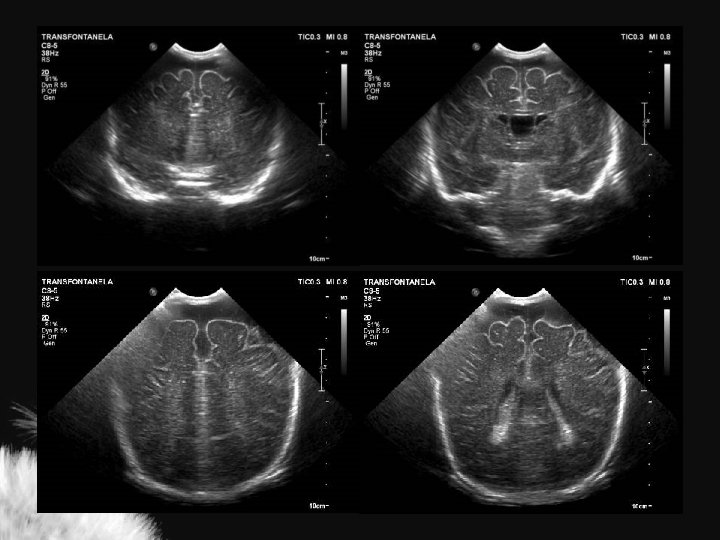

MACROCRANIA

Macrocrania • Macrocrania benigna hidrocefalia benigna da infância, coleção extra axial benigna da infância • Condições patológicas: • US – Coleções anecóicas – Formato em V – Sulcos e giros proeminentes – Ventrículos normais ou proeminentes – Pia-aracnoide com ecogenicidade normal – Higroma subdural – Hematoma subdural – Abscesso secundário a meningite – Coleções ecogênicas – Formato em U – Sulcos e giros deslocados ou achatados – Ventrículos alargados – Pia-aracnoide hiperecogênica

Mc Cluney et al. AJNR 13: 1335 -1339 Chen et al. Radiology 201: 389 -392

Hidrocefalia benigna da infância – sinal da veia cortical positivo

Coleção subdural – sinal da veia cortical negativo